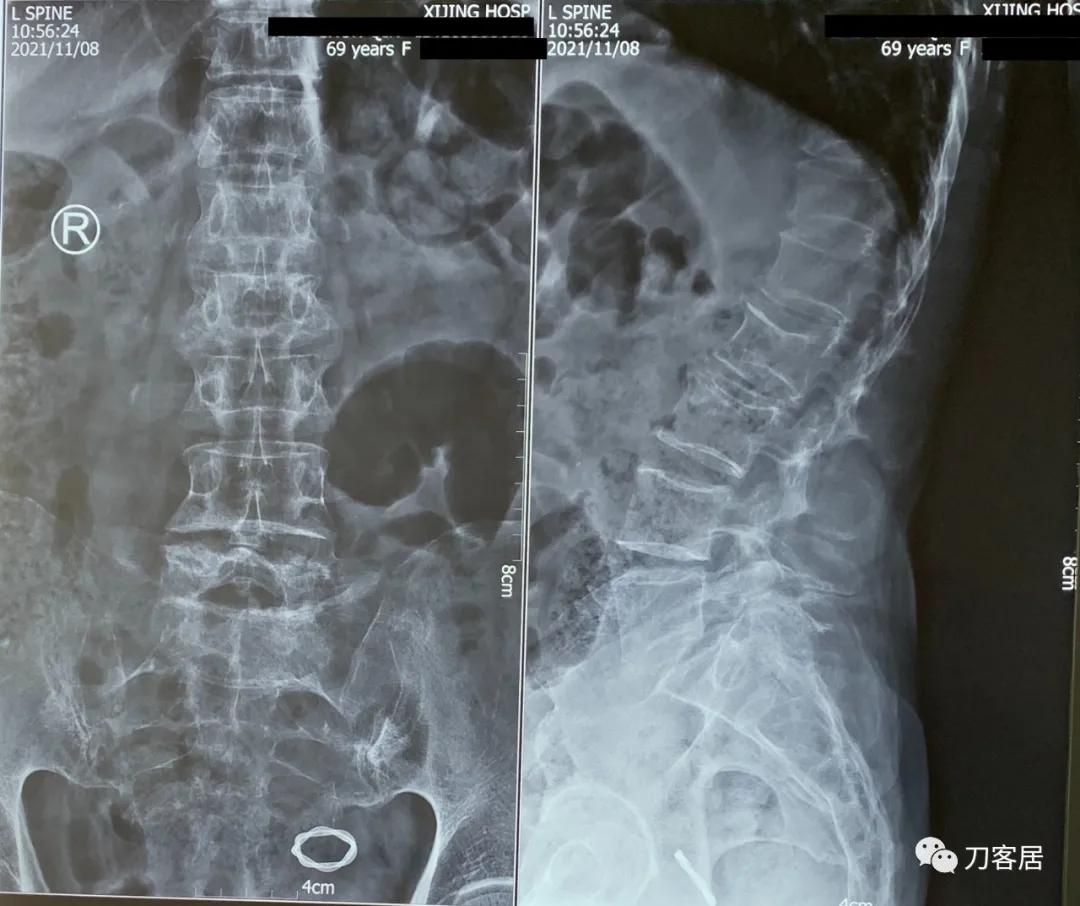

患者为69岁,女性, 就诊日期:2021年11月8日。因晨起腰痛2天,就诊当日有缓解。疼痛自腰部放射至大腿后侧。2004-2005年曾有腰椎骨折病史,保守治疗后愈。

腰椎X线片提示腰5峡部裂,腰5椎体前滑脱1度,膝关节X线片提示退变增生,右侧髌股关节增生、狭窄、骨刺形成。骨密度提示骨质疏松,T值最低-3.3。2014年曾换心脏瓣膜手术,长期服用华法林,辅酶Q10, 盐酸曲美他嗪。

诊断:骨质疏松症,腰5峡部裂,腰5椎体前滑脱1度,双膝关节创伤性关节炎。